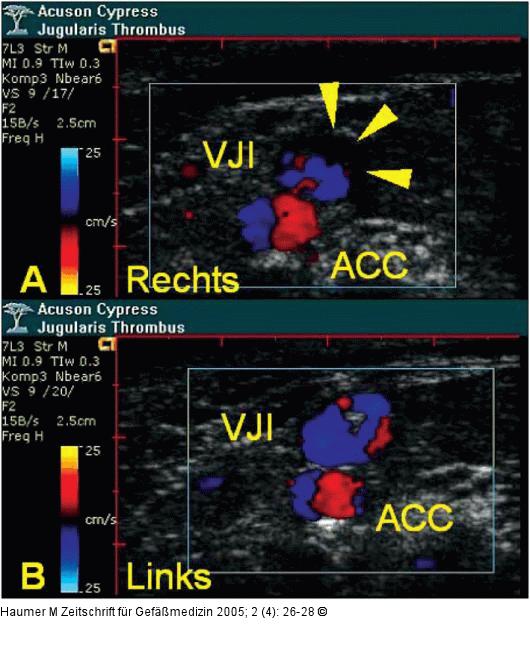

Abbildung 2: Vena jugularis - Thrombose Darstellung der großen Halsgefäße im Querschnitt mit farbkodierter Flußdarstellung (Acuson Cypress(R), 7L3 Linear-Transducer; 7 MHz). Thrombotischer Randsaum in der V. jugularis interna dextra (Pfeilspitzen in A), umspülter zentraler Fibrinfaden in der V. jugularis interna sinistra (B). [VJI: V. jugularis interna; ACC: A. carotis communis]. |

Darstellung der großen Halsgefäße im Querschnitt mit farbkodierter Flußdarstellung (Acuson Cypress(R), 7L3 Linear-Transducer; 7 MHz). Thrombotischer Randsaum in der V. jugularis interna dextra (Pfeilspitzen in A), umspülter zentraler Fibrinfaden in der V. jugularis interna sinistra (B). [VJI: V. jugularis interna; ACC: A. carotis communis]. |